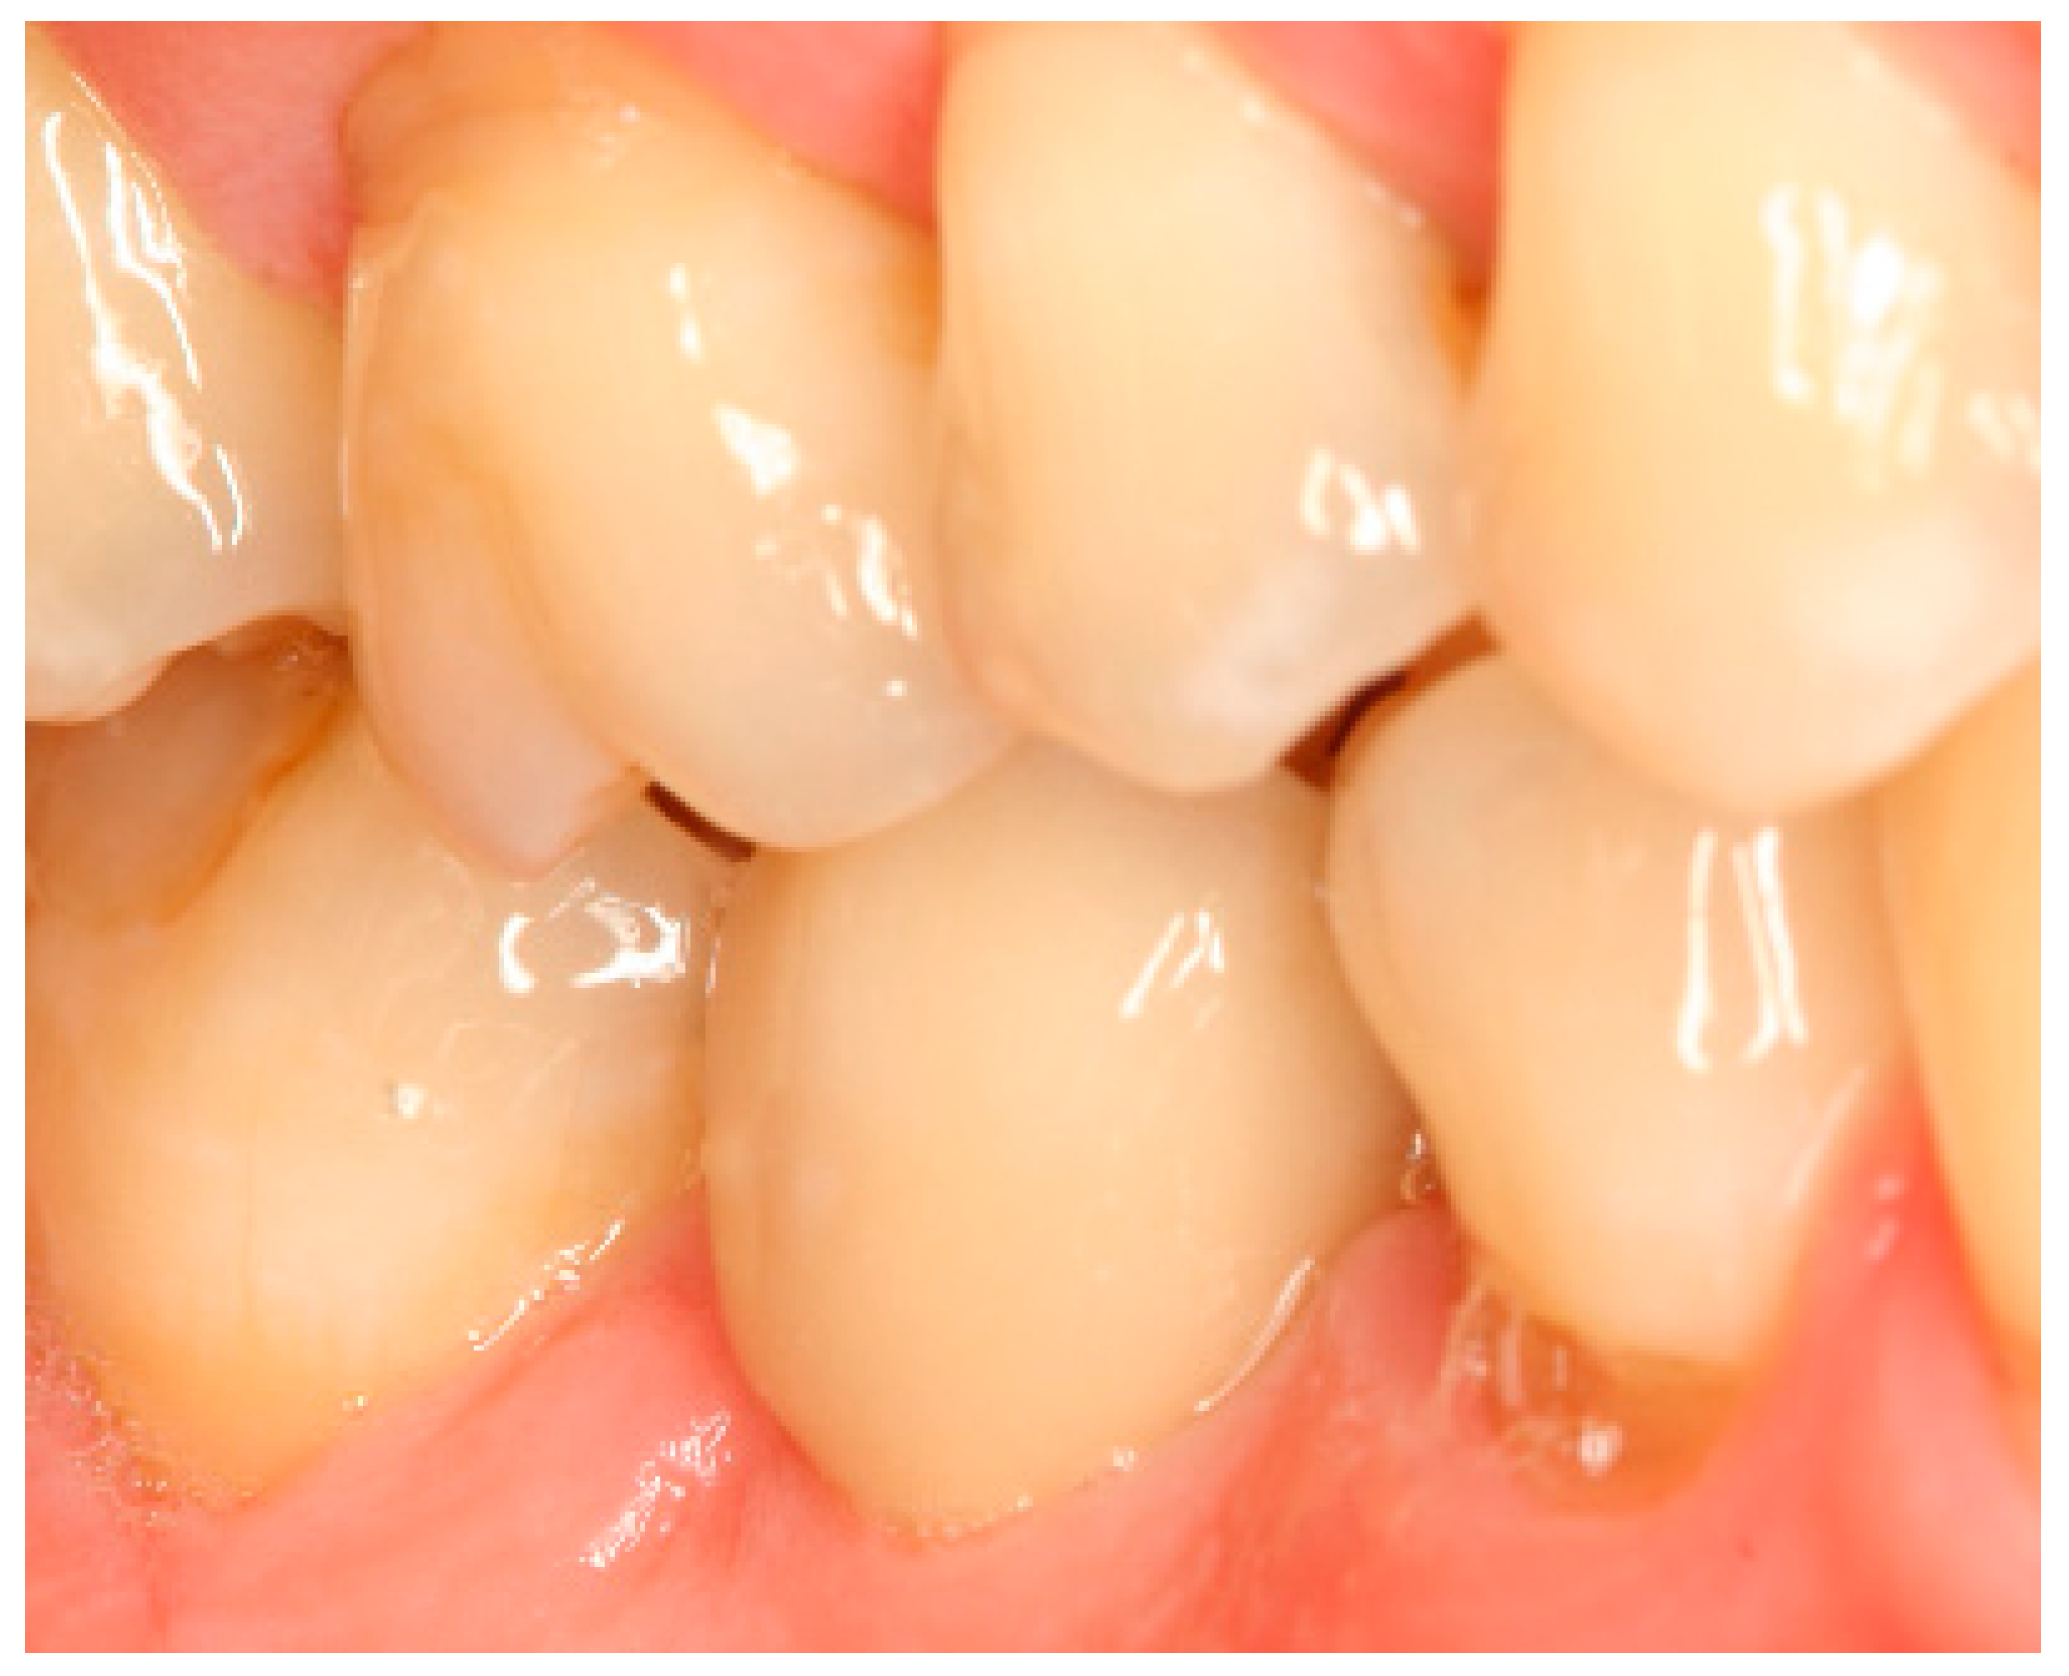

Appendix A. Exemplary Photographs and Radiographs from a Patient at Different Examination Time Points and a Positive Outcome